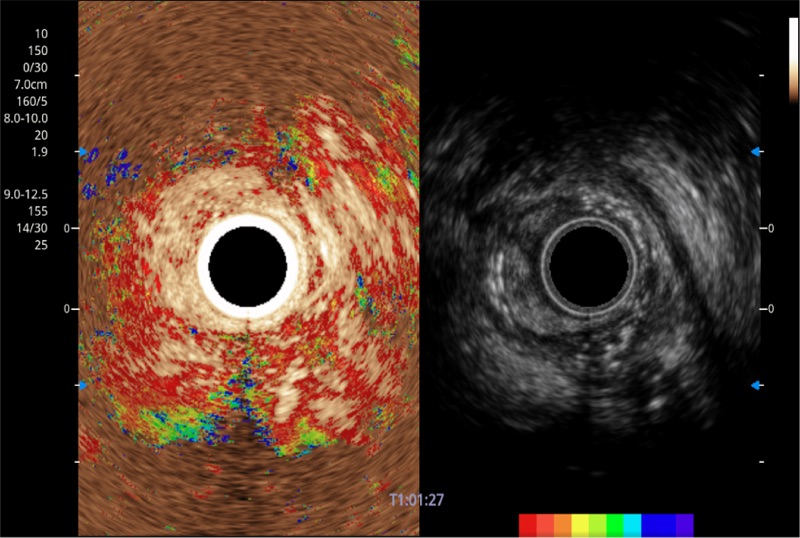

具有四种造影成像效果

食管内间质瘤清晰显像

清晰显示胆总管及周围血管分布

肝左叶和肝静脉的横截面